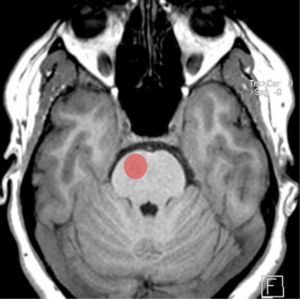

Since Millard-Gubler syndrome affects the ventrocaudal (anteromedial) pons, it does not damage the cranial nerve nuclei but rather the fascicles. The spinothalamic tract and the medial meniscus are not affected as they are dorsal to the lesion; thus somatosensory symptoms would be unexpected.[2] Figures 1 and 2 illustrate the location of Millard-Gubler syndrome.

Figure 2: Location of damaged area (red circle) on a normal T1 weighted MRI in Millard-Gubler syndrome.[5] Adapted from case courtesy of Frank Gaillard. https://radiopaedia.org/?lang=us. Radiopaedia.org. From the case https://radiopaedia.org/cases/14278?lang=us. rID: 14278. Used under CC BY-NC-SA 3.0 https://creativecommons.org/licenses/by-nc-sa/3.0/, via Radiopaedia